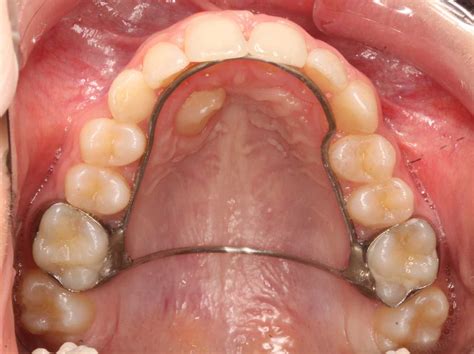

Tras el estudio del caso se inicia el tratamiento de ortodoncia. Si el canino se ha desviado mucho de su posición no erupcionará simplemente con la creación de espacio: será necesaria su exposición y tracción. Para ello, es necesario realizar una exposición quirúrgica del canino incluido y colocar un elemento de tracción para guiar su erupción hacia la posición correcta.

El primer paso es el estudio en profundidad del caso. Para ello, se solicitan radiografías, como las panorámicas o tomografía computerizada (TAC); herramientas esenciales para evaluar la posición y la trayectoria de erupción de los caninos incluidos.